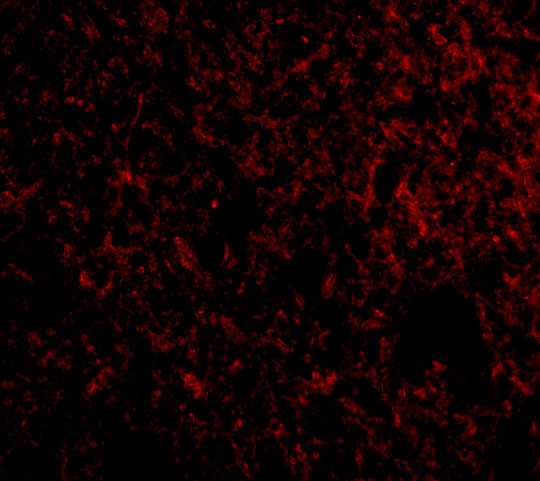

As a member of the NUPR1/RELB/IER3 survival pathway, can offer pancreatic ductal adenocarcinoma with remarkable resistance to cell stress, such as starvation or gemcitabine therapy. .

| Gene Name: | IER3 |

DIF-2; DIF2GLY96; Differentiation-dependent gene 2 protein; expressed in pancreatic carcinoma; gly96, mouse, homolog of; IEX-1; IEX1death protein; IEX-1L; Immediate early protein GLY96; Immediate early response 3 protein; immediate early response 3; immediately early gene X-1; PRG1PACAP-responsive gene 1 protein; Protein DIF-2; Protein PRG1; radiation-inducible immediate-early gene IEX-1